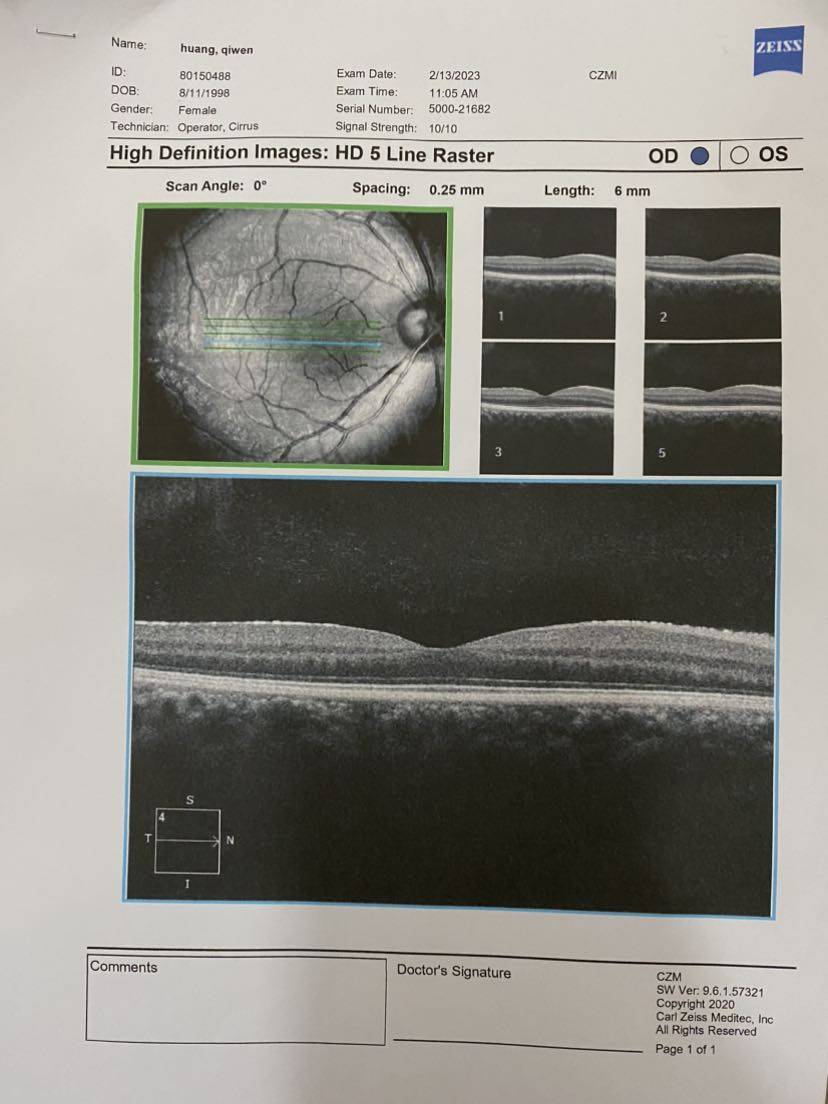

最后把所有报告记录一下,医生说要保管好。千万不能折,那就拍照先留个底吧~

【眼部ct】

哇,这个报告好仔细。

第一次看到这么详细的报告!蛙蛙下次去风湿免疫科复查的时候问问看~

眼部ct多少钱